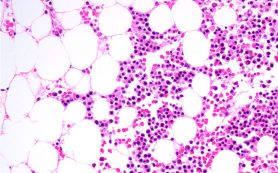

Initial findings from a multi-national open-label phase Ib study of inhibitory drug therapy for relapsed or refractory acute myeloid leukemia (AML) have demonstrated a complete response in up to 50 percent patients say researchers at The University of Texas MD Anderson Cancer Center .

The patients, age 60 years or older, received therapy with venetoclax in combination with cobimetinib or idasanutlin. The clinical trial followed patients who received therapy for a prior blood disease and who were not eligible for cytotoxic therapy.